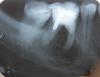

common_78 Опубликовано 13 ноября, 2007 Поделиться Опубликовано 13 ноября, 2007 Здравствуйте!Подскажите, можно ли как-нибудь спасти нижнюю шестёрку (на снимке). Там как я понял гранулёма или киста...Можно ли попытаться удалить её хирургическим путём? То есть вырезать через десну. Или удалить один корень, а второй оставить?Готов на любые эксперименты, любимый зуб, не хочется терять! Ссылка на комментарий

Zlata-doctor Опубликовано 13 ноября, 2007 Поделиться Опубликовано 13 ноября, 2007 Судя по этому снимку, у Вас имеются абсолютные показания к удалению данного зуба.Все варианты лечения, которые Вы перечислили, имеют право на жизнь , но не в Вашем случае. Также я бы рекомендовала Вам попросить Вашего доктора посмотреть соседние зубы, там имеется как минимум кариес проксимальных поверхностей, а может быть и периодонтит (особенно седьмого зуба). Ссылка на комментарий

Doc Опубликовано 13 ноября, 2007 Поделиться Опубликовано 13 ноября, 2007 Здравствуйте! Подскажите, можно ли как-нибудь спасти нижнюю шестёрку (на снимке). Там как я понял гранулёма или киста... Можно ли попытаться удалить её хирургическим путём? То есть вырезать через десну. Или удалить один корень, а второй оставить? Готов на любые эксперименты, любимый зуб, не хочется терять! К хЕрургу его. А снимок - шедевр! Пошел в копилку. Ссылка на комментарий

Штаматолог Опубликовано 13 ноября, 2007 Поделиться Опубликовано 13 ноября, 2007 А снимок - шедевр! Пошел в копилку. Ага, новое слово в армировании депульпированных зубов... любыми ненужными мелкими металлическими предметами. Ссылка на комментарий

Bier Опубликовано 14 ноября, 2007 Поделиться Опубликовано 14 ноября, 2007 а что это такое? какая-то зап.часть от стоматологического оборудования? Наверное, штифта под рукой не оказалось?.. вот ведь, доктор-рационализатор. Наверняка это был мужчина, женщины так консервативны ... :-) имеется в виду штифт, находящийся не в канале, а в толще пломбы Ссылка на комментарий

DoctorDim Опубликовано 14 ноября, 2007 Поделиться Опубликовано 14 ноября, 2007 (изменено) имеется в виду штифт, находящийся не в канале, а в толще пломбы Да просто второй штифт медиально поставить хотели, но перфорнули корень! Сумму за лечение оговорили, видимо, заранее, поэтому ненужный более второй штифт решили просто в пломбу замуровать! Так что всё, типа, по-честному - за сколько заплатил, столько и получил! Ну, а перфорацию - в качестве приятного бесплатного дополнения! Изменено 14 ноября, 2007 пользователем DoctorDim Ссылка на комментарий

DoctorDim Опубликовано 14 ноября, 2007 Поделиться Опубликовано 14 ноября, 2007 Да просто второй штифт медиально поставить хотели, но перфорнули корень! Сумму за лечение оговорили, видимо, заранее, поэтому ненужный более второй штифт решили просто в пломбу замуровать! Так что всё, типа, по-честному - за сколько заплатил, столько и получил! Ну, а перфорацию - в качестве приятного бесплатного дополнения! Или, что тоже вероятно, штифт взяли слишком длинный, отпилили лишнюю часть, но не выбросили, как обычно делается, а в пломбу замуровали.... Ну, тоже - умереть - не встать.... Ссылка на комментарий

Doc Опубликовано 14 ноября, 2007 Поделиться Опубликовано 14 ноября, 2007 Или, что тоже вероятно, штифт взяли слишком длинный, отпилили лишнюю часть, но не выбросили, как обычно делается, а в пломбу замуровали.... Ну, тоже - умереть - не встать.... Вообще штифтами такого диаметра пломбировать такие каналы это уже перебор... Я вообще даже молчу, о том, что анкерами вообще ничего пломбировать не надо бы... Ссылка на комментарий